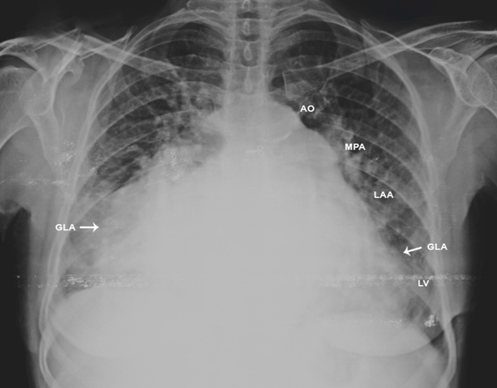

Figure 15. X-ray chest PA (postero-anterior) view---arrows showing the extension of giant left atrium (GLA) to both chest walls.

In 1849, Hewett was the first to describe the giant left atrium in autopsy series of mitral valve disease [11]. When LA enlarges, it moves rightward and Hurst described the giant left atrium as one that touches the right lateral thoracic wall (giant left atrial syndrome) in chest X-ray and it is almost always caused by rheumatic mitral valve disease [12] with predominant mitral regurgitation than mitral stenosis and atrial fibrillation is mostly present in this condition. In 1984, Piccoli, et al consider giant left atrium when the cardio-thoracic ratio in the chest X-ray is > 0.7 in addition to a left atrial anteroposterior diameter of > 8 cm in transthoracic echocardiography [13]. Massive dilatation of the left atrium occurs in all directions, may reach both chest walls as in Figure 15 and particularly to the right and sometimes to the left as in Figures 3 and 9 [14] Giant LA is rarely observed in non-rheumatic mitral valve involvement and it does not occur in mitral regurgitation due to other causes. Severe mitral regurgitation due to MVP does not produce a giant left atrium since there is no associated primary left atrial disease as shown in Figures 1 and 2. Phua and Brownsberger, et al reported giant left atrium due to mitral valve prolapse [15] and the largest “ non-rheumatic” giant left atrium reported in mitral valve prolapse measured 12 x 13 cm [16]. A giant left atrium associated with PML (posterior mitral leaflet) prolapse) due to severe mitral regurgitation as a result of chordal rupture with rheumatic etiology was shown in Figures 4 to 8. The largest reported giant left atrium due to untreated rheumatic heart disease measured 19.3 x 14.7 cm [17] and 20 x 16.8 cm [18]. Owen, et al misinterpreted a giant left atrium as right-sided pleural effusion and punctured [19], the postmortem examination revealed a severely enlarged left atrium occupying the entire thoracic cavity and this is the first published case of ‘giant left atrium’, a term that was introduced by Fisher, et al [20] in 1956. Schwartzman, et al performed a CT –guided biopsy in a giant left atrium believing it to be a malignant mass [21]. There is no definition of a giant left atrium based on LA volume and an anteroposterior atrial diameter > 65 mm as ‘giant left atrium’, corresponding to 1.6 times the normal value (< 40>Figure 17 and the cut off’s are arbitrary whether an atrium is severely dilated or giant.

In mitral regurgitation, the left atrial size is proportionately related to compliance and the dilated left atrium compensates for increased stress by an initial increase in compliance. This reservoir effect of a large left atrium is beneficial to protect the lungs from pulmonary hypertension and edema [28],[29]. Increased left atrial and pulmonary pressures, in case of very large left atrium ( > 60 mm) provide the substrate as a structural precursor of atrial fibrillation [30],[31] which contributes further atrial dilation in mitral valve disease [32]. The dilated atrium requires more energy to pump blood and lose its elastic properties due to myocarditis, succumbs to deformational change, limiting Laplace’s law application in chronic mitral regurgitation and becomes larger with an increase in LA volume. For an LA diameter of 6 cm, the estimated volume of atrium exceeds 300 ml [33]. The increased LA volume may complicate thrombus formation due to potential stasis with thromboembolic events. The enlarged left atrium may compress the bronchial tree (widening of carinal angle (splaying of carina) > 120 ₀ as shown in Figure 3, stenosis of left main bronchus), left laryngeal nerve (hoarseness due to left vocal cord paralysis- Ortner’s syndrome [34],[35]), inferior and middle lobes of right lung (atelectasis, infection) [36], postero-basal part of left ventricle as in Figure 17 (hemodynamic instability) and esophagus (dysphagia). Isolated LV compression by Giant LA is defined as Type 1 [37], both LV and bronchopulmonary compression is defined as Type II [38] Giant left atrium. Nigri reported a rare complication of giant left atrium, pushing the heart to the right side of the chest and mimicking as dextrocardia [39],[40]. The left atrium extends more to the left side forming the left atrial appendage which becomes convex in the left heart border (third Mogul sign) just below the pulmonary trunk when it is dilated (normally it should be flat or slightly concave) and makes a “4-bump” left heart border as in Figure 3 and 9 that includes the aortic knob, main pulmonary artery, left atrial appendage, and the left border of left ventricle. In mitral stenosis, the body of left atrium is larger than normal and it never produces a giant left atrium, but giant left atrium with rheumatic mitral stenosis was reported [41] and it may be associated with massive thrombus formation as shown in Figures 21 to 24.